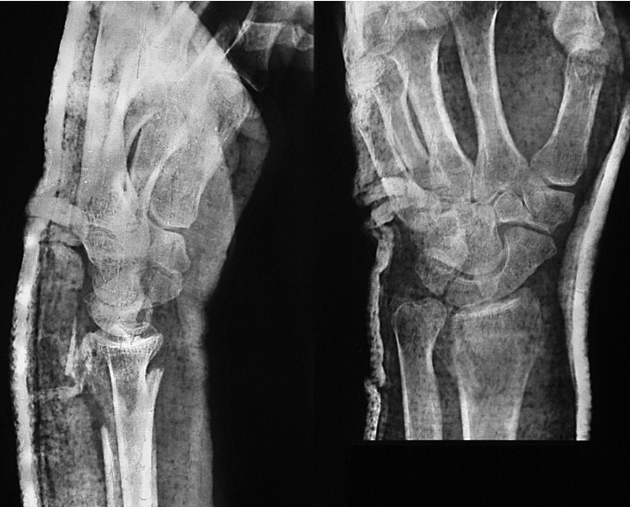

患者,女,51岁。因右腕摔伤后肿痛、畸形、活动受限,急诊就诊诊断为右桡骨远端骨折。行闭合牵引复位,石膏托外固定。拍片复查,桡骨远端背侧因骨折的粉碎性质而缺损巨大,背侧的皮质骨碎片向远端移位至桡腕关节间隙水平并嵌于腕背软组织中无法闭合复位(图2-1)。桡骨远端背侧因缺乏可靠的皮质骨支撑而存在骨折继发移位、掌倾角向背侧倾斜且移位的皮质骨碎片潜在刺激背侧软组织、磨损伸肌腱的风险,增加发生关节疼痛和功能障碍的可能性,于是行桡骨远端骨折切开复位,人工骨植入,超关节外固定架固定术。

图2-1 桡骨远端背侧因骨折的粉碎性质而缺损巨大,背侧的皮质骨碎片向远端移位至桡腕关节间隙水平并嵌于腕背软组织中无法闭合复位